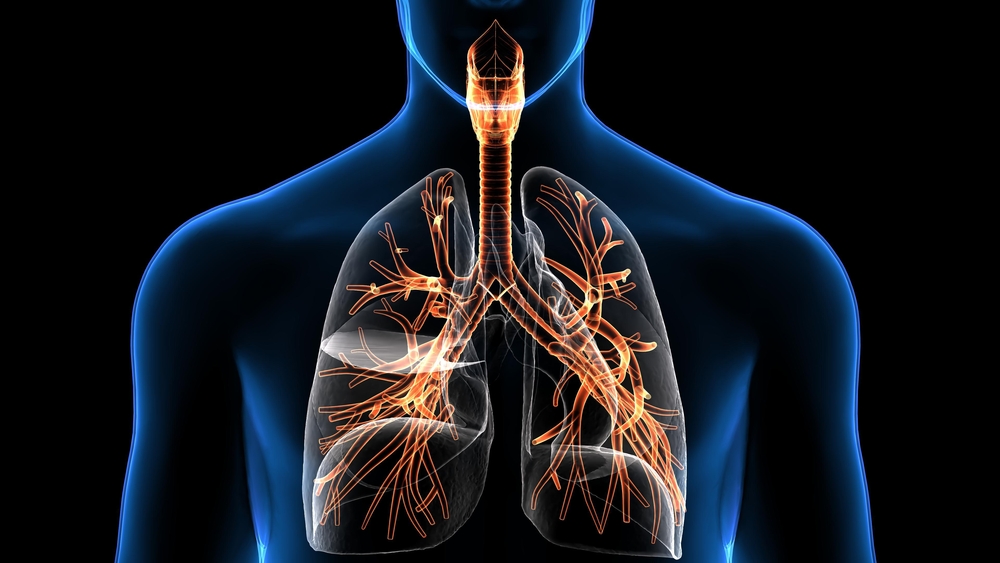

सामान्यतया, लामो दौड वा केही किलोमिटर पैदल हिँडेपछि सास फेर्न गाह्रो हुन्छ। यस्ता क्रियाकलाप गर्दा रक्तचाप बढेपछि श्वासप्रश्वासमा समस्या आउनु सामान्य हो, तर थोरै समय मात्र हिँड्दा वा सिँढी चढ्दा पनि यस्तो समस्या हुन्छ ? यदि हुन्छ भने, तपाईंले सावधानी अपनाउनु आवश्यक छ, यो गम्भीर स्वास्थ्य समस्याको संकेत पनि हुन सक्छ। सामान्यतया मुटु वा फोक्सोको रोगसँग सास फेर्न गाह्रो हुने कुरालाई जोडिन्छ तर यी दुई अंगमा समस्याका कारणले मात्र सास फेर्न गाह्रो हुन सक्छ भन्ने छैन।

स्वास्थ्य विज्ञहरूका अनुसार मुटु सम्बन्धि रोग वा दम जस्ता श्वासप्रश्वाससम्बन्धी समस्याका कारण मानिसहरूलाई प्रायः सास फेर्न गाह्रो हुन सक्छ। तर यो आवश्यक छैन कि प्रत्येक पटक सास फेर्न गाह्रो हुनु कारण यी दुई कारणहरू मात्र हुन्छन्। धेरै कारणले सास फेर्न गाह्रो हुन सक्छ। यस्तो अवस्थामा यसको पछाडिको वास्तविक कारणको मूल्याङ्कन गरी समयमै उपचार गर्नुपर्छ। आउनुहोस् यसबारे राम्रोसँग छलफल गरौँ….

शरीरमा पर्याप्त मात्रामा अक्सिजन नपुग्दा सास फेर्न गाह्रो हुन सक्छ। यस्तो अवस्थामा स्वाभाविक रूपमा व्यक्तिले छिटो सास फेर्न प्रयास गर्छ। सास फेर्न गाह्रो हुनुलाई मेडिकल भाषामा डिस्पेनिया भनिन्छ। यस समस्याको धेरै चिकित्सा र गैर-चिकित्सा कारणहरू हुन सक्छन्। एलर्जी, दम, मुटुरोग, मोटोपना, क्षयरोगजस्ता समस्याबाट पीडित व्यक्तिलाई श्वासप्रश्वासको समस्या बढी हुन्छ।

स्वास्थ्य विज्ञहरूका अनुसार श्वासप्रश्वासको समस्यालाई फोक्सो र मुटुको समस्यासँग मात्र जोड्नु ठीक होइन। धेरै मानिसहरूमा, मृगौला र मांसपेशी सम्बन्धित समस्याहरूले पनि सास फेर्न गाह्रो हुन सक्छ। यही कारणले गर्दा यो रोगको वास्तविक कारण समयमै निदान गर्न आवश्यक छ। यसलाई बेवास्ता गर्दा वा मुटुको समस्याको मात्र उपचार गर्दा यसले अन्य धेरै ठूला रोगहरू निम्त्याउन सक्छ।